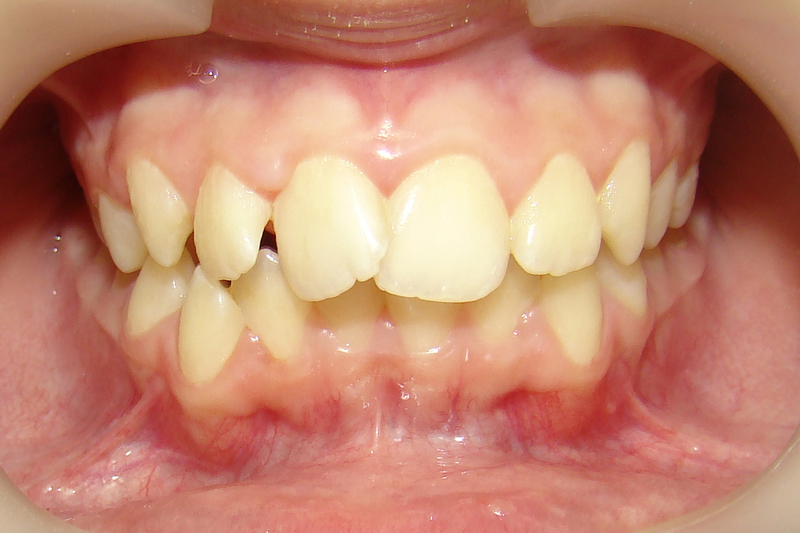

А это уже молодой человек 10 лет. Тоже получилось справиться без удаления. Хоть оно и было показано. Но мальчик очень упорно носил специальные аппаратики и резиночки. Покажу со всех сторон. Этот случай победил в конкурсе на конференции